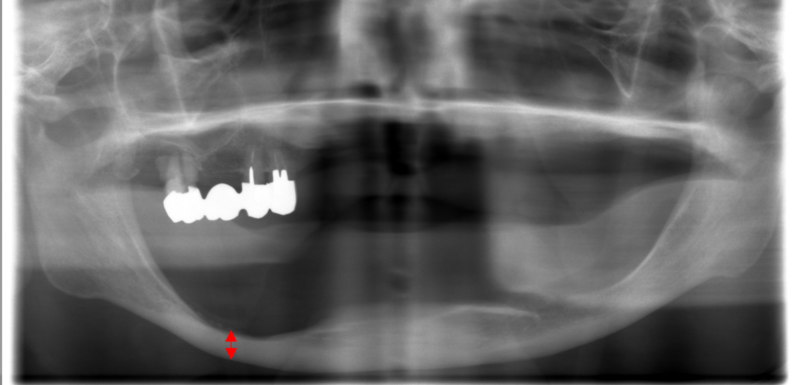

お口の中の写真を見るとやはり向かって左下が凹んでいます。それに対して、上あごにご自分の歯が4本残っています。

向かって左下が凹んでしまった理由として考えられることのひとつは、しっかりと残っている上の歯がハンマーの様に下の入れ歯を叩くので、どんどん凹んでしまった可能性があります。非常に難しい症例です。

また上の歯が矢印のように噛んでくると下の歯は内側ではなく外側に並んで噛ませないといけませんので、交叉咬合(※)といわれる噛み合わせになります。これは入れ歯の噛み合わせとしては、バランスを保てないので難しくなります。

お口の中の写真